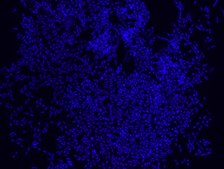

Eubacteria probe recognizes most bacteria as it is complementary to a portion

of 16S rRNA found in almost all bacteria.9,10

FISH technique was successfully used to identify different bacteria with the universal bacterial probe in various samples such as, pure culture (as described in the figure legends), blood cultures10,11, periapical tooth lesions12, saliva13, biofilms from voice prostheses14, subgingival biofilm15, aortic wall tissue16, buccal epithelial cells, pure culture and cell culture17, intestine tissue embedded in paraffin18, necrotizing fasciitis and pure culture19, colon sections embedded in paraffin20,21, cancer tissues22,23, environmental samples24 and gut of the medicinal leech25. The probe can also be used for combined technique of FISH and Flow cytometric analysis. 9,26,27